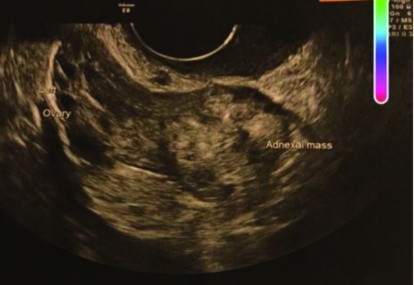

Primary ovarian ectopic pregnancy

Primary ovarian ectopic pregnancy is one of the rarest forms of ectopic pregnancy. Its incidence after natural conception ranges from one in 2,000 to one in 60,000 deliveries and accounts for 3% of all ectopic pregnancies.1 It is estimated that ovarian pregnancy occurs in one in 25,000-40,000 pregnancies.2 It...